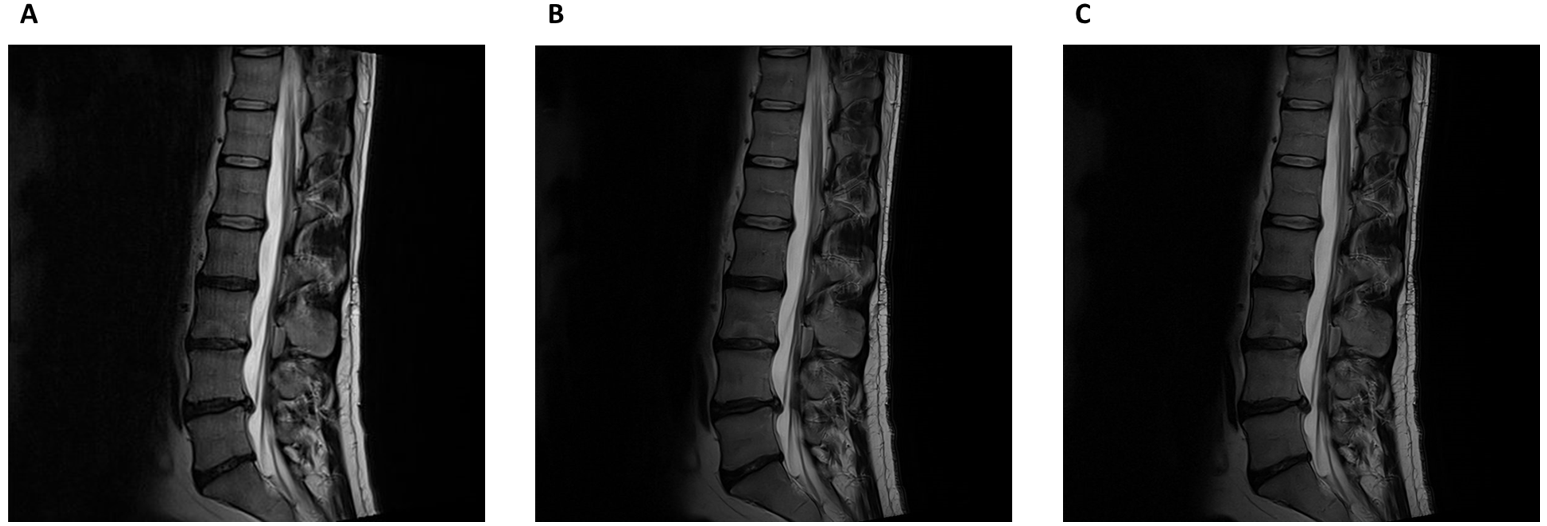

Case study 4: Deep Resolve Boost in lumbar spine imaging on Siemens Sola (XA51)

Dr Matthew Birkbeck, Newcastle upon Tyne NHS Foundation Trust